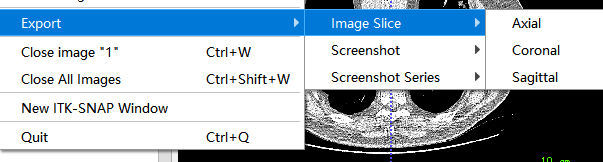

Add Another Image可以进行不同DICOM文件的融合,比如不同段的CT扫描图像save Image -> main Image可以对文件进行另存export导出文件:

Image Slice单对切面的导出,导出的格式为png, 不包含标注的图像Screenshot / Screenshot Series将图片导出为截图的格式,包含了图片的标注信息。与导出切片不同,导出的截图与图像在软件中的显示是一样的,常用于一些图像的说明